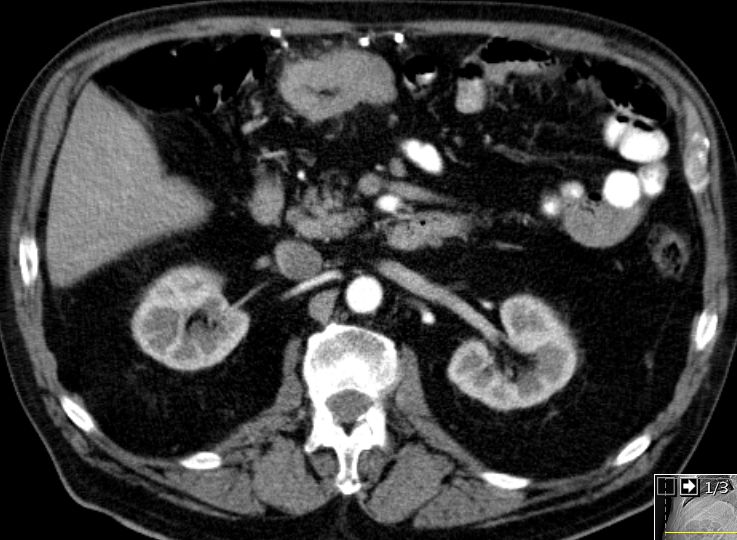

| Colon transversum | 74-jähriger Mann mit einem Colon-Karzinom pT3a pNo(0/17) M1hep L1 V1 G3.![]() |